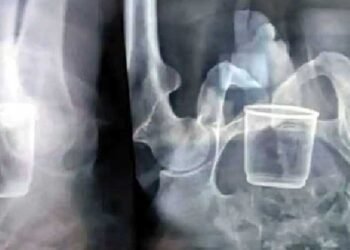

పొట్టలోకి గ్లాసు ఎలా వెళ్లిందబ్బా…?!

చిన్నపిల్లల చేతుల్లో ఏవైనా వస్తువులుంటే తీసేస్తూంటాం. ఎందుకంటే, వాళ్లు ఆ వస్తువులను నోట్లో పెట్టుకుంటే గనక గొంతులో ఇరుక్కునే ప్రమాదం గానీ, పొట్టలోకి వెళ్లే ప్రమాదం గానీ ...